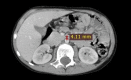

Background: Superior mesenteric artery syndrome (SMAS), also known as Wilkie's syndrome, is a rare disease that mainly presents as intestinal obstruction with a variable incidence ranging from 0.013 to 0.3% (Salehzadeh et al. in Case Rep Gastrointest Med, 2019, 10.1155/2019/3458601). In this syndrome, the third part of the duodenum, located between the abdominal aorta and the superior mesenteric artery, is wholly or partially obstructed (Mosalli et al. in J Pediatr Surg 46:e29-31, 2011). Case presentation An 8-years-old Arabian male patient was admitted to the gastrointestinal department at the pediatric hospital in Damascus, Syria, with complaints of chronic abdominal pain and periodic vomiting since he was two years old. At the age of Seven, he was diagnosed with appendicitis, and after two months of persistent symptoms, he was diagnosed with an umbilical hernia. Finally, after a long time of suffering, he was diagnosed with SMAS and underwent a successful surgical operation. After 3 months of follow-up, he was in good health with no symptoms.